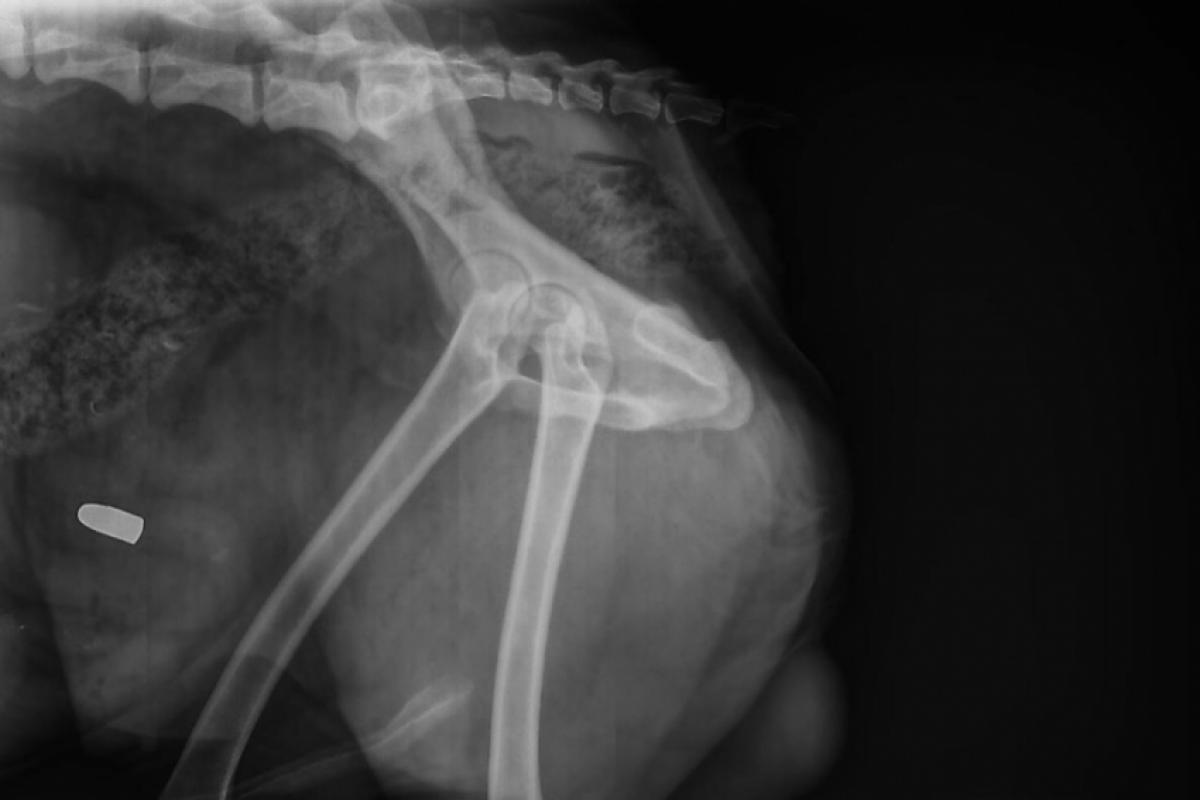

Bala alojada no cachorro após disparo em Franca